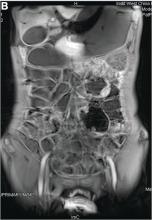

The urine and stool tests yielded normal results. Tests for autoimmune diseases showed negative results. Gastroscopy, colonoscopy, and abdominal CTA (Figure A) were repeated and yet again produced normal results. Magnetic resonance enterography showed parts of the small bowel walls thickening in the left upper abdomen (Figure B).